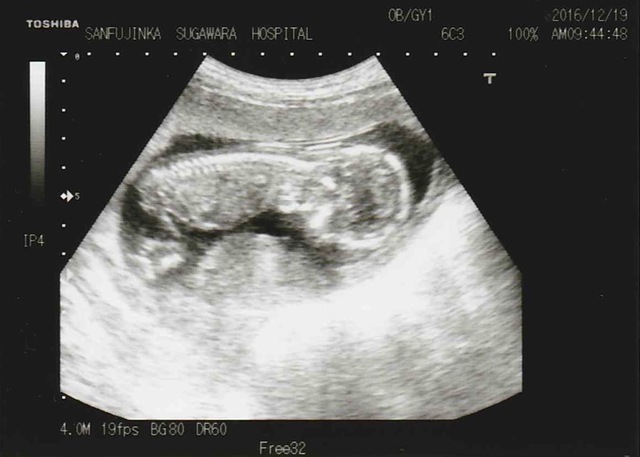

14週6日(14w6d・性別不明)|lala5 さん(31歳)

エコー写真撮影時のエピソード:

去年、婦人科検診を受けると子宮頸部高度異形成と診断され手術を受けました。その為子宮が短くなり妊娠しても流産や早産などのリスクもある事をお医者さんから告げられてました。

なので妊娠はなかなか出来ないものかと不安でしたが今年の3月に体調悪い日が続き、吐き気と熱っぽさで風邪かと思っていましたが病院を受診してみると妊娠していることがわかりました。

すでに私の体調悪さは悪阻が始まっていたようで先生はエコー写真を3Dで撮って下さいました。小さいながら人間の形をしているお腹の中の赤ちゃんに感動して涙が止まらなかったです。その時のエコー写真です。